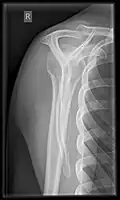

X-ray

Projectional radiography views of the shoulder include:

- AP-projection 40° posterior oblique after Grashey

The body has to be rotated about 30 to 45 degrees towards the shoulder to be imaged, and the standing or sitting patient lets the arm hang. This method reveals the joint gap and the vertical alignment towards the socket.[26]

-

CR. shoulay film. -